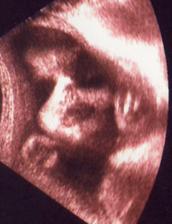

Čekání na Kateřinku... (UZ)

Čekáme holčičku - Kačenku. Dokud jsme jméno vybírali, říkali jsme jí Melounka. I.TP máme 29. 2., II.TP 2. 3. 2008. a III.TP je 13. 3. 2008.